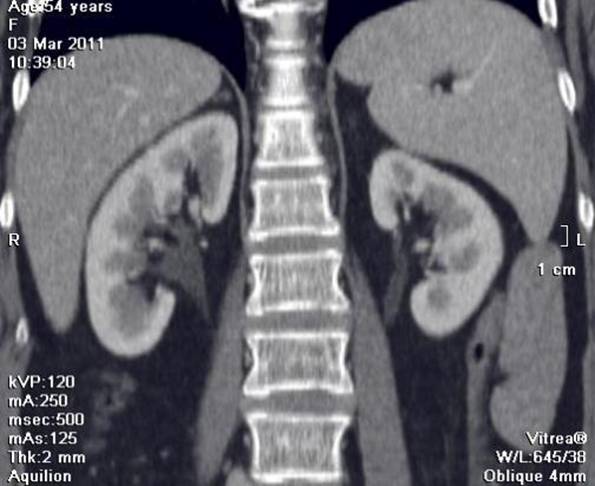

Дані інструментальних

методів

дослідження

(УЗД нирок та

сечових

шляхів, екскреторна

урографія, сканографія, комп’ютерна

томографія)

допомагають

встановленню

діагнозу.

При

рентгенологічному, ультразвуковому

дослідженні

нирок, комп’ютерній

томографії

знаходять

розширення і

деформацію

ниркових

мисок

різного

ступеня

вираженості, асиметрію,

зморщення

нирок.